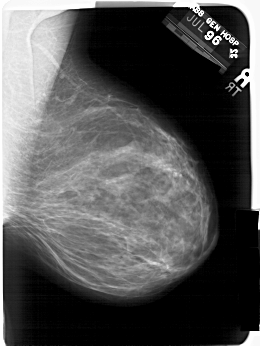

A_1408_1.LEFT_MLO

LEFT_MLO LINES 6871 PIXELS_PER_LINE 4786 BITS_PER_PIXEL 12 RESOLUTION 43.5 OVERLAY